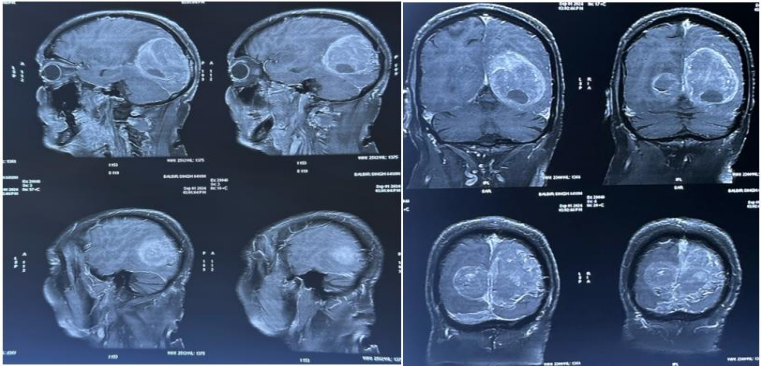

Following input from the neurosurgery team, an excisional biopsy of the occipital lesion was performed in Nov 24,  Histological analysis revealed a spindle cell neoplasm, with immunohistochemical staining demonstrating positivity for CD117, DOG1, and CD34, consistent with a metastatic gastrointestinal stromal tumor (GIST). (Fig 7)

Fig 7 : spindle cell neoplasm, with immunohistochemical staining demonstrating positivity for CD117, DOG1, and CD34, consistent with a metastatic gastrointestinal stromal tumor (GIST).

antarmuka fokus mahjong daya pengguna aktifaws grid serasi mahjong dasar tahapan terjagaaws jejak mekanisme mahjong arah fase lanjutanaws kajian wild berantai mahjong interaktif analitisaws kesesuaian persentase layanan mahjong seluler lanceraws pendalaman persentase mahjong gerak wild mutakhircorak langka mahjong tumbuh perlahan berubahgerak mahjong adaptasi mekanisme pemakai sekarangnalar scatter mahjong malam putaran ekstratempo mahjong kaitan mekanisme keadaan terkinialur permainan mahjong cepat scatter wilddalam hitungan detik scatter wild mahjongmenyatukan naluri pola scatter hitam mahjongmomen mahjong permainan berbalik arahmomen singkat mahjong dinamika permainanperpaduan insting pola scatter hitam momentperubahan drastis mahjong ways scatter wildscatter wild mahjong datang polasekejap berubah scatter wild mahjong wayssensasi baru mahjong lebih scatter wildenergi scatter emas irama reel mahjongevolusi reel mahjong balutan mistisintervensi cepat emas momentum lamakemunculan mendadak naga emas mahjongketika scatter naga emas aktif mahjongnaga emas muncul arah spin mahjongnaga emas ritme mahjong ways berubahrahasia rtp tinggi balik scatter hitamsaat scatter naga emas alih irama reelscatter hitam kunci lonjakan rtp mahjonge5 scatter wild memberikan sentuhan baru di setiap spin mahjong ways 2e5 scatter wild menghidupkan suasana permainan mahjong ways 2e5 scatter wild mengubah pola permainan mahjong ways 2 secara signifikane5 setiap putaran mahjong ways 2 terasa berbeda dengan scatter wilde5 strategi adaptif berbasis analisis rtp hariane5 strategi berbasis data dan algoritma untuk analisis momentume5 strategi berkembang berkat data rtp hariane5 strategi memahami algoritma untuk mengidentifikasi momentum ideale5 strategi membaca pola algoritma demi menangkap momentum optimale5 strategi modern mengandalkan evaluasi rtp hariane5 strategi responsif dengan dukungan evaluasi rtp hariane5 strategi terukur dengan analisis rtp hariane5 struktur scatter dan wild terlihat jelas berkat analisis sistem moderne5 tanpa disadari kombinasi ini sering mengarah ke scatter di mahjong wins 3e5 teknik evaluasi algoritma untuk mendapatkan momentum yang tepate5 teknik observasi sistem untuk analisis momentum yang lebih presisie5 terungkap formasi ini sering jadi awal munculnya scatter di mahjong wins 3e5 transformasi digital rtp live berkat artificial intelligence inovatife5 transformasi ritme mahjong ways 2 dipicu oleh kekuatan scatter wilde5 wajib tahu pola tersembunyi ini sering menghasilkan scattere5 applee5 bananae5 candye5 doge5 eaglee5 falcone5 geminie5 horsee5 indiae5 japananalisa pola mahjong ways rutinanalisis kinerja heuristik variansi gameanalisis pola mahjong ways hariananalisis pola mahjong ways kebiasaanera baru mahjong wins bonus optimalgebrakan bonus mahjong wins mekanisme efisieninsight pola mahjong ways rutinkajian pola mahjong ways rutinkomparasi heuristik variansi game digitalledakan bonus mahjong wins sistem efektifmahjong wins bonus sistem generasi baruobservasi pola mahjong ways harianpendekatan algoritma heuristik variansi gameperbandingan model heuristik variansi gamerahasia bonus mahjong wins sistem cerdasrangkuman pola mahjong ways harianringkasan pola mahjong ways harianstudi pola mahjong ways hariantinjauan heuristik variansi game digitaltinjauan pola mahjong ways harianalur sombol mahjong kemunculan scatterdari rtp mahjong bermain lebih efektifjejak scatter mahjong putaran tenangkejutan scatter wild simbol mahjong arahkemunculan simbol ganda membuat mahjongketika grid mahjong scatter semakin dekatketika rtp mahjong pola mulai lebih jelasketika scatter wild ritme simbol mahjongketika scatter wild titik sesi mahjong waysketika susunan simbol mahjong ritme scattermemahami rtp mahjong cara bermain lebihpergerakan simbol mahjong scatter wildpergeseran mahjong ketika scatter hadirsaat rtp mahjong terbaca baik strategisaat scatter hadir simbol mahjong bergeserscatter wild dinamika simbol mahjongstabilitas putaran mahjong pola scattersusunan baru reel mahjong scatter emassusunan mahjong wins mengandung scattersusunan simbol mahjong diam pola scatterrm menguak keunikan mahjong wins sudut pandang teknisrm cara memahami pergerakan mahjong ways tenaga ekstrarm mahjong wins standar baru industri hiburan digitalrm rahasia ketahanan mahjong ways eksis gempuran gamerm pentingnya memahami transisi level mahjong wins mendalamrm strategi mengatur tempo mahjong ways kendali permainanrm peran kecerdasan buatan mekanisme mahjong wins adilrm alasan keberhasilan mahjong ways mencuri perhatian analisrm mempelajari struktur dasar mahjong wins efisiensi putaranrm inovasi desain mahjong ways kesan bermain responsifrm teknik observasi mahjong wins jarang dibahas dampakrm cara mempertahankan fokus dinamika mahjong ways cepatrm eksplorasi fitur tersembunyi mahjong wins ritme terbaikrm mahjong ways integrasi teknologi modern keamanan nyamanrm analisis faktor pendukung mahjong wins digemari generasirm langkah efektif menyesuaikan perubahan sistem mahjong waysrm mengintip proses pengembangan mahjong wins kualitas penggunarm analisis data membantu membaca arah mahjong waysrm menemukan titik temu insting logika mahjong winsrm transformasi besar mahjong ways menghadirkan tantangan menarikmengungkap simbol langka nasib drastismisteri besar kombinasi simbol langkamisteri simbol langka keberuntungan besarsimbol langka misterius ubah hiduprahasia simbol langka nasib cepattransformasi bonus mahjong wins sistem efektifmahjong wins suguhkan bonus sistem modernsuguhan bonus efisien mahjong winsefektivitas sistem bonus mahjong winsmahjong wins hadirkan bonus sistem optimaloke76cincinbetaqua365slot gacorstc76samurai76TOBA1131samurai76 login